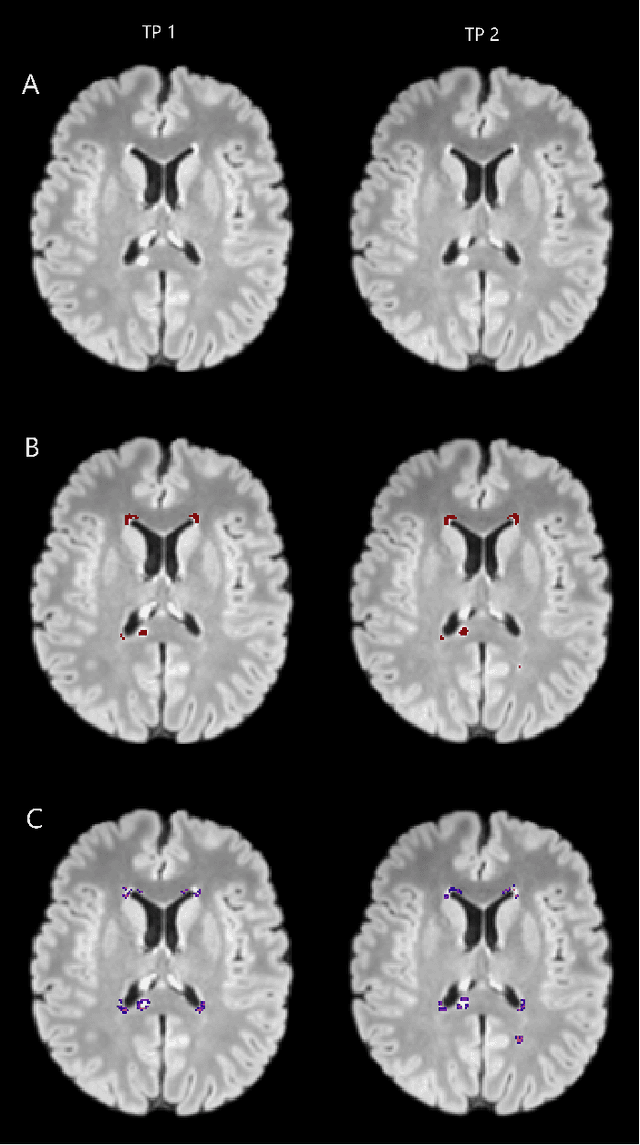

Abstract:The detection of new or enlarged white-matter lesions in multiple sclerosis is a vital task in the monitoring of patients undergoing disease-modifying treatment for multiple sclerosis. However, the definition of 'new or enlarged' is not fixed, and it is known that lesion-counting is highly subjective, with high degree of inter- and intra-rater variability. Automated methods for lesion quantification hold the potential to make the detection of new and enlarged lesions consistent and repeatable. However, the majority of lesion segmentation algorithms are not evaluated for their ability to separate progressive from stable patients, despite this being a pressing clinical use-case. In this paper we show that change in volumetric measurements of lesion load alone is not a good method for performing this separation, even for highly performing segmentation methods. Instead, we propose a method for identifying lesion changes of high certainty, and establish on a dataset of longitudinal multiple sclerosis cases that this method is able to separate progressive from stable timepoints with a very high level of discrimination (AUC = 0.99), while changes in lesion volume are much less able to perform this separation (AUC = 0.71). Validation of the method on a second external dataset confirms that the method is able to generalize beyond the setting in which it was trained, achieving an accuracy of 83% in separating stable and progressive timepoints. Both lesion volume and count have previously been shown to be strong predictors of disease course across a population. However, we demonstrate that for individual patients, changes in these measures are not an adequate means of establishing no evidence of disease activity. Meanwhile, directly detecting tissue which changes, with high confidence, from non-lesion to lesion is a feasible methodology for identifying radiologically active patients.